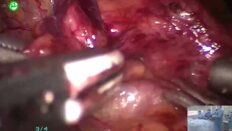

Опубликованы видеозаписи Конференции «Рабочие встречи Евразийской Ассоциации урологов», трансляция которого проходила 22 марта 2025 года на портале Uro.TV.